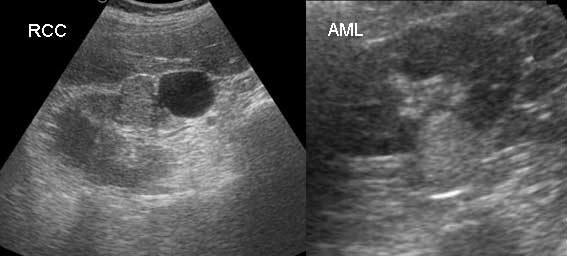

Ну что же, давайте посмотрим внимательно, сравним изображения.

На картинке слева - RCC, опухоль имеет эхогенность чуть выше эхогенности паренхимы почки, но ниже чем эхогенность центрального эхокомплекса и периренальной клетчатки.

Справа - AML, эхогенность опухоли примерно равна эхогенности и центрального эхокомплекса и периренальной клетчатки. Причем создается впечатление что опухоль и клетчатка сливаются друг с другом, что часто затрудняет оценку распространенности опухоли и ее правильного измерения.